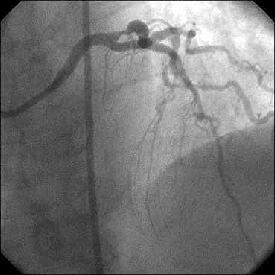

�Ǘ��72�Ώ����Brisk factor��HT, HL, DM�ł��B

��2�T�ԑO�̔��ǂƎv����Recent MI�ł��BLAD#7: total��Tristar3.0�~18?�����

�܂����B

����LCx ostium: 75%�ł��B������PCI���悤�Ǝv���̂ł����A�ǂ̂悤��strategy

���l������ł��傤���H

���Ȃ݂ɓ��@�ł�DCA�g�p�o���҂͂��܂���B

DCA�ł���l��A��Ă���A�Ƃ����I�������܂߂Č䏕��������K���ł��B

�X�������肢���܂��B

|

|

|

|

|

����������������������������������������������������������������������������